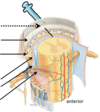

State the following meningeal layers shown